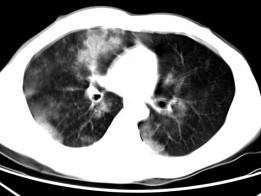

男,28岁,外伤后1小时行胸部CT如图,其最可能的诊断为 ( )A、肺癌B、双肺挫伤C、肺脓肿D、肺囊肿E、肺炎

问题 男,28岁,外伤后1小时行胸部CT如图,其最可能的诊断为 ( )

选项 A、肺癌 B、双肺挫伤 C、肺脓肿 D、肺囊肿 E、肺炎

答案 B